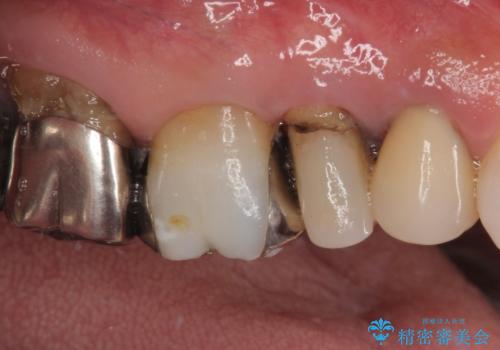

- 奥歯が咬みにくいことを主訴に来院された患者様です。

奥歯以外にも、全体的に大きな問題を抱えていらっしゃったので、全顎的な治療を行うこととしました。

抜かなければならない歯は抜歯し、保存できそうな歯については残すための処置を行った上で、抜歯するかどうかを判断することとしました。

歯周病ではなかったため、インプラントに必要な治療期間で全体の治療を終了させることができました。

1回の診療時間を長く取ることで、2回目の診療後にはすべてを仮歯にすることができ、長年気にされていた前歯の見た目を速やかに改善することができました。

オールセラミッククラウンによってとても自然に仕上がり、また、安定した咬み合わせとなったことで、患者様には大変満足していただきました。